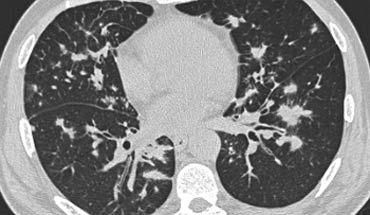

Dưới đây là hai ví dụ về viêm phổi quá mẫn bán cấp.

Có thể thấy các nốt trung tâm tiểu thùy bờ không rõ dạng kính mờ.

Đây là một trường hợp khác của viêm phổi quá mẫn bán cấp.

Có thể thấy hình mờ mờ nhạt ở trung tâm các tiểu thùy thứ cấp (mũi tên) với vùng dưới màng phổi được bảo tồn.

Hình ảnh HRCT này cũng cho thấy hình mờ trung tâm tiểu thùy mờ nhạt ở bệnh nhân HP bán cấp.

Lưu ý ranh giới không rõ của các nốt trung tâm tiểu thùy này.

Đôi khi các hình mờ trung tâm tiểu thùy có hình thái dạng nốt rõ hơn như trong trường hợp này.